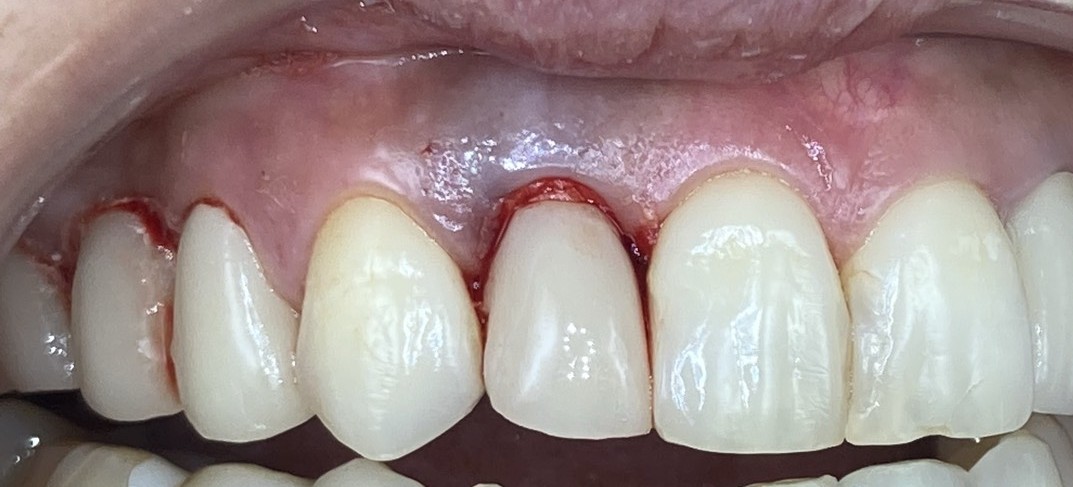

<オペから約3ヶ月後>

最終の被せ物を装着。歯ぐきの血色も良くなっています。

この方法ですと元々あった歯の周りの歯ぐきや骨がほとんど減らないため見た目がとても自然です。治療期間も短く、治療期間中も仮歯がしっかり入るので不便が少ないです。

何より、過去の治療方法に比べて腫れや痛みも少ないのです。

今回のケースでも歯ぐきの血色が回復し、綺麗に治っていることがわかります。

処置内容:

右上側切歯を抜歯、ガイドを使用してインプラントを埋入、即日に仮歯を装着。

2ヶ月半後に最終の型取りスキャンをして上部構造を装着。

治療期間:

3ヶ月

治療費:

55万(税込)

考えられるリスク・副作用:

手術後の痛み、腫れ、インプラント周囲炎